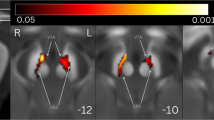

Compared with the PD-RBD- group, the PD-RBD+ group presented greater QSM values in the left rectus gyrus and lower QSM values in the right superior frontal gyrus dorsolateral regions (p < 0.05, cluster-level FWE-corrected; Table 2, Fig. 1a). Compared with the HCs, the PD-RBD+ patients presented greater QSM values in the bilateral SNpc, right precentral gyrus, and left middle cingulate cortex and lower QSM values in the right postcentral gyrus. Additionally, the PD-RBD- patients had a lower QSM value in the left inferior cerebellum (p < 0.05, cluster-level FWE-corrected; Table 2, Fig. 1a).

The results were visualized in the MNI coordinate system. a comparison of QSM. b. comparison of χpara. Warm colors indicate regions where the susceptibility values of the PD-RBD+ group are greater than those of the PD-RBD- group, as well as regions where the susceptibility values of the PD-RBD+ group and PD-RBD- group are greater than those of the HC group. The cool colors indicate the opposite. QSM quantitative susceptibility mapping, χpara paramagnetic susceptibility mapping, PD-RBD+ Parkinson’s disease with secondary rapid eye movement sleep behavior disorder, PD-RBD- Parkinson’s disease without rapid eye movement sleep behavior disorder.

Compared with the PD-RBD- group, the PD-RBD+ group presented a lower χpara value in the left middle temporal gyrus (p < 0.05, cluster-level FWE corrected; Table 2, Fig. 1b). Compared with the HC group, the PD-RBD+ group presented greater χpara values in the bilateral SNpc (p < 0.05, cluster-level FWE-corrected; Table 2, Fig. 1b), exhibiting a similar pattern to that observed for the QSM value. Compared with the HCs, the PD-RBD- patients presented greater χpara values in the left inferior temporal gyrus and left middle temporal gyrus and lower χpara value in the left cerebellar lobule IX (p < 0.05, cluster-level FWE-corrected; Table 2, Fig. 1b).